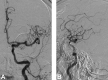

Fentanyl is a potent opioid used commonly in acute care because of its rapid onset and short duration of action. It has fewer side effects when compared with commonly available opioids, such as morphine and hydromorphine. We report an unusual side effect of transient aphasia following fentanyl administration. A 61-year-old female presented for an elective embolization of a periophthalmic artery aneurysm. She developed immediate episodes of aphasia on two separate occasions following administration of intravenous (IV) fentanyl. The high lipid solubility explains the rapid onset of action of fentanyl as it rapidly passes through the blood-brain barrier and through cell membranes. Immediately following the administration of fentanyl, the patient developed aphasia. There were no other clinical or neurological imaging findings that could account for these symptoms. We believe that aphasia may be an unusual side effect of fentanyl, and it is something clinicians should be aware of.